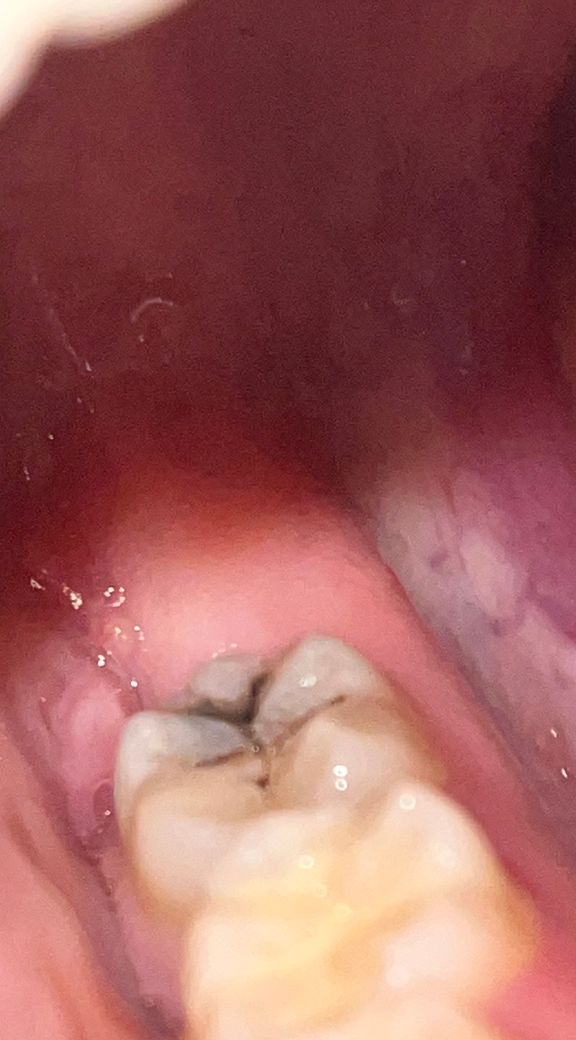

사랑니 발치 하얀색 떨어지고 피나요 ㅜㅜ

사랑니 발치한지 3일정도 되었는데요 밥 먹다가 저도 모르게 발치 부위를 조금 건들였는데 하얀색 덩어리 진게 조금 없어지고 그 부위에 피가 계속 나네요 어떻게 된걸까요?

사랑니 발치 후에 며칠간은 미세하게 출혈이 생길 수는 있습니다. 해당 부분 자극하지 않게 조심하면 됩니다.

발진 한 부위가 자극이 되었다면 출혈이 될 수 있습니다. 발치한 부위를 자극하지 않는다면 괜찮아지는 경우가 많습니다. 해당 부위에 대해 출혈이 된다면 네 군데 거즈를 물고 있는 것을 권유 드립니다.

사랑니 발치한곳이 아직다 아물지 않아서 피가 조금씩은 날수 있습니다. 큰문제가 잇는건 아니니 걱정하지 않으셔도 될것같습니다.